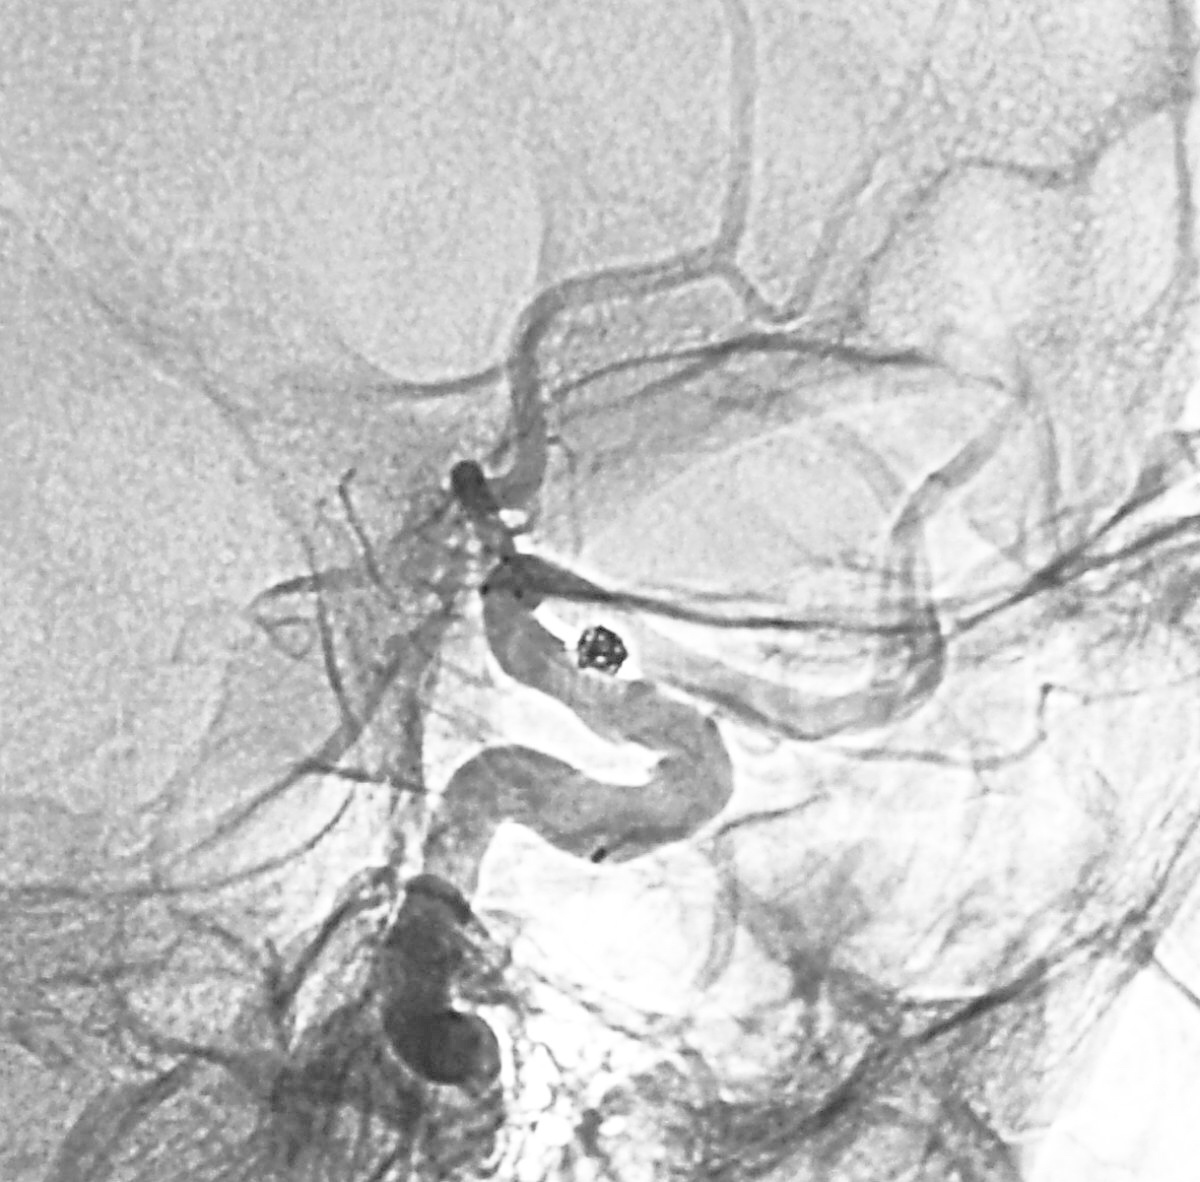

Solitaire 4×15支架(绿线)跨瘤颈半释放,压住微导管(红线)。

经微导管向瘤腔内送入首枚弹簧圈(QC-2-4-3D)。

继续送入两枚QC-1.5-2-Helix,完全栓塞动脉瘤,部分圈突入载瘤动脉。

结束栓塞后不要直接撤管,要先把微导管往远心端送,使管头脱离瘤腔,再缓慢回撤。

微导管撤出后,完全释放Solitaire支架,可见突入载瘤动脉的弹簧圈被压回瘤腔。

术后左颈内动脉工作位造影和蒙片。